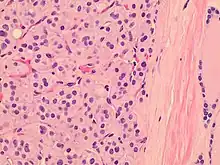

Histopathology of a Hürthle cell adenoma

Hürthle cells are characterized as enlarged epithelial cells. These cells, when stained with hematoxylin-eosin show as pink. This is due to the abundant mitochondria and granular eosinophilic matter within the cells' cytoplasm. These cells are often found in the thyroid. The thyroid is a butterfly-shaped organ, responsible for producing various hormones for metabolism. These cells are often benign, but they can be malignant and metastasize. Hürthle cells are resistant to radiation, but can be treated using radioactive iodine treatment.[4]